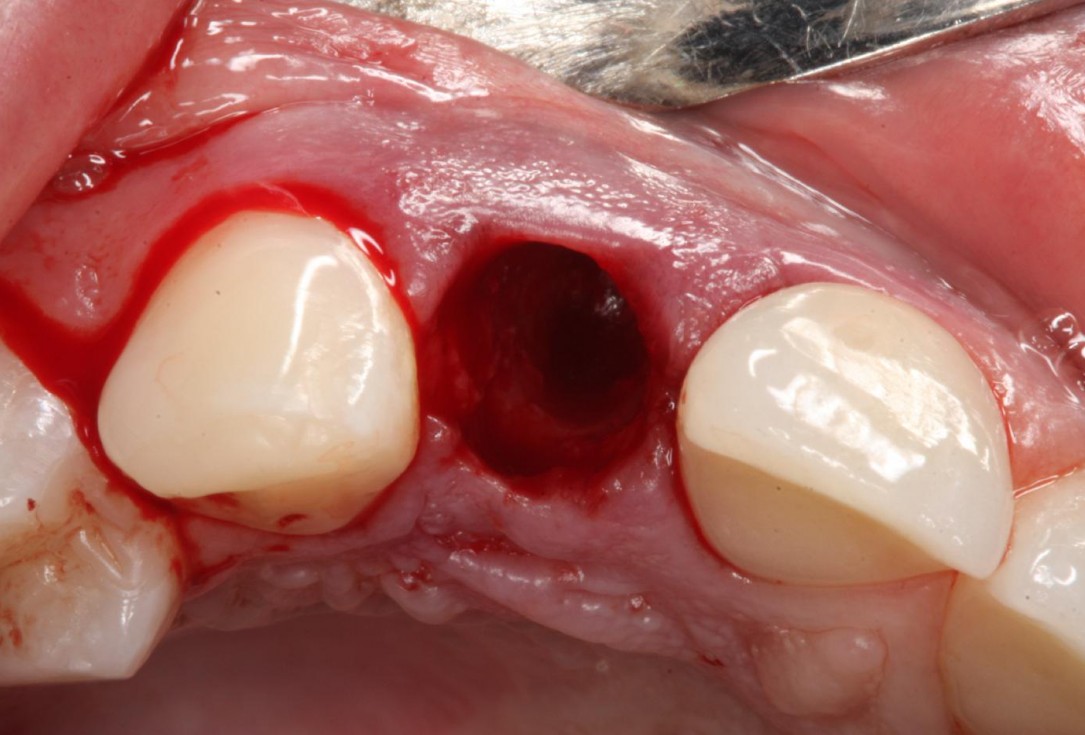

2/12 - Atraumatic tooth extractionSoft tissue thickening at immediate implant placement and GBR with mucoderm® and maxgraft® - Dr. A. Puisys

Intact socket following atraumatic tooth extraction

Alveolar socket before soft and hard tissue augmentation

Initial clinical situation with traumatic loss of tooth 21

Tooth extraction due to root fracture